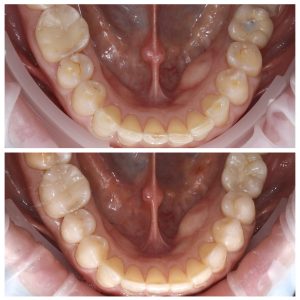

Visų dantų plombavimas dėl amžinių pokyčių ir bruksizmo

Šiuo atveju anksčiau pastebėjus dantų nudilimus, kuriuos lėmė amžius ir bruksizmas, ir anksčiau pradėjus nešioti apsauginę kapą (dantų kapa miegui), dantų nudilimai galėtų būti mažesni.

• Stiprus visų dantų nudilimas (priežastys – amžiniai pokyčiai ir bruksizmas);

Kompleksinis dantų gydymas apėmė šiuos etapus:

Visų dantų plombavimas prieš ir po Nudilusių dantų estetinis plombavimas prieš ir poVisų nudilusių dantų plombavimas prieš ir poViršutinis dantų lankas prieš ir po plombavimoApatinis dantų lankas prieš ir po plombavimo